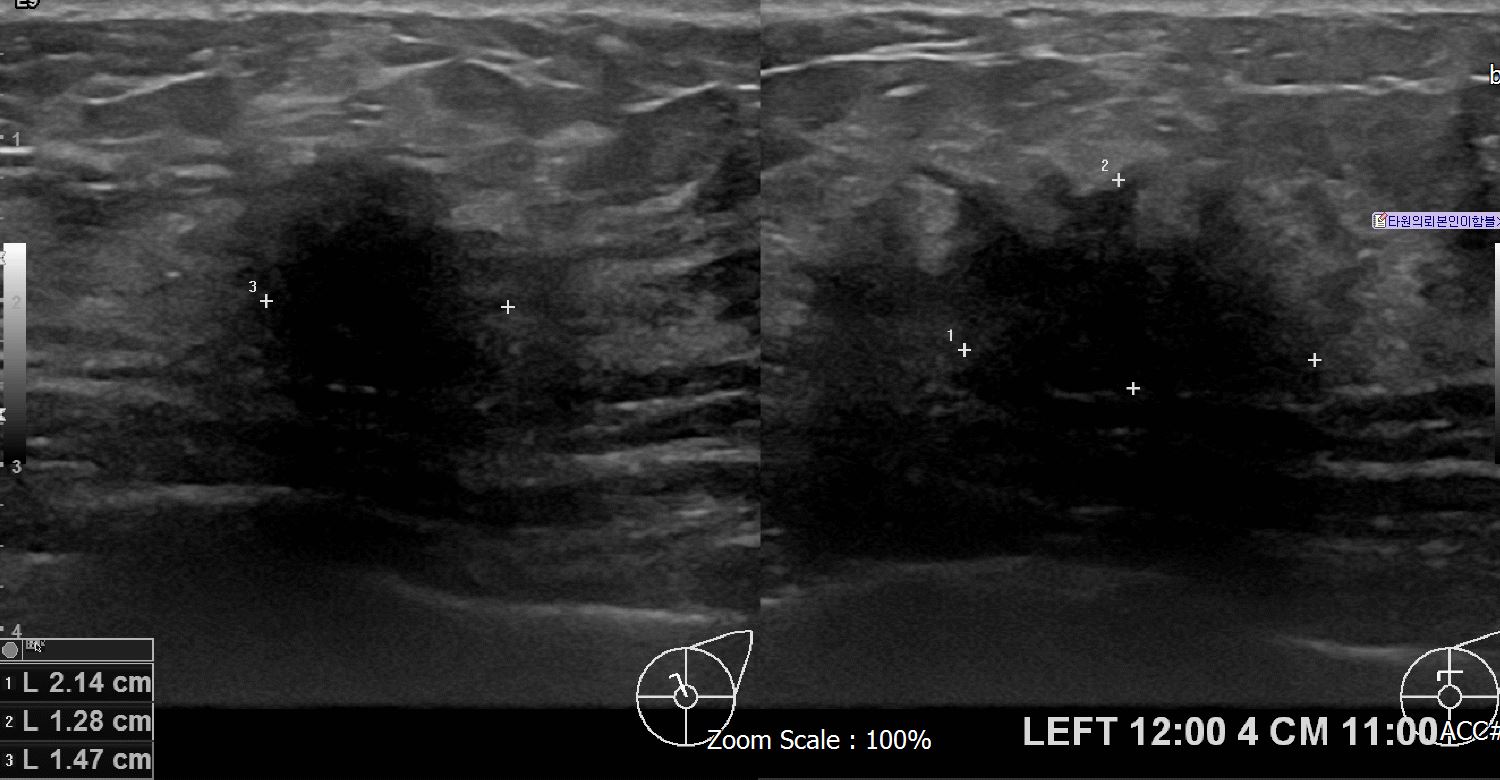

아산유외과 개원후 618번째 유방암진단

상기환자 외부검사상이상소견으로 내원하신 50대 여성으로 좌측유방에 의심스러운혹있어 조직검사시행후 유방암진단되었습니다.